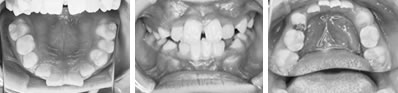

取り外しのできる簡単な装置で治療した例

各種検査で確認をした後に、上顎前歯を外に出すことが適当と判断された症例です。本人の性格やご家族の方の希望も考慮して治療方針が決定されます。取り外しのできる簡単な装置を用いて治療を開始しました。

前歯の反対咬合と凸凹を解消した8歳

前歯の反対咬合と、それに合せて歯肉が下がっていることが心配されました。下顎の凸凹も問題でした。

上顎左側の2番目の永久歯(側切歯)が反対咬合です。まだ乳歯も多く残る歯並びですが、全体に凸凹が認められます。